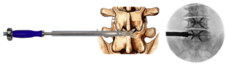

■大阪院で新たに始まる先進治療「フローレンス法」について

フローレンス法とは、欧州や南アメリカを中心に導入されている先進的な脊柱管狭窄症の治療です。

これまで脊柱管狭窄症の治療は保存療法で効果がなかった場合は外科手術での対応が主であり、約1週間~2週間の入院が必要でした。

フローレンス法は「入院することなく日帰りで」治療することができる画期的な治療法です。ようやく日本で日帰り脊柱管狭窄症治療ができるようになりました。

保存治療で改善せず、脊椎固定術等の全身麻酔で行われる外科的手術を避けたい患者様にお勧めしています。

治療イメージ図